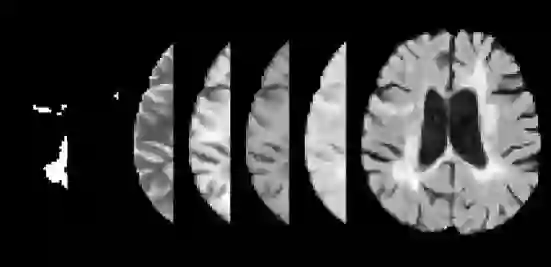

Precision medicine for chronic diseases such as multiple sclerosis (MS) involves choosing a treatment which best balances efficacy and side effects/preferences for individual patients. Making this choice as early as possible is important, as delays in finding an effective therapy can lead to irreversible disability accrual. To this end, we present the first deep neural network model for individualized treatment decisions from baseline magnetic resonance imaging (MRI) (with clinical information if available) for MS patients. Our model (a) predicts future new and enlarging T2 weighted (NE-T2) lesion counts on follow-up MRI on multiple treatments and (b) estimates the conditional average treatment effect (CATE), as defined by the predicted future suppression of NE-T2 lesions, between different treatment options relative to placebo. Our model is validated on a proprietary federated dataset of 1817 multi-sequence MRIs acquired from MS patients during four multi-centre randomized clinical trials. Our framework achieves high average precision in the binarized regression of future NE-T2 lesions on five different treatments, identifies heterogeneous treatment effects, and provides a personalized treatment recommendation that accounts for treatment-associated risk (e.g. side effects, patient preference, administration difficulties).

翻译:为治疗慢性病,如多发性硬化综合症(MS)的精密医学涉及选择一种最能平衡对个别病人的功效和副作用/偏重的治疗方法。尽早作出这一选择很重要,因为寻找有效疗法方面的拖延可能导致不可逆转的残疾累积。为此,我们为慢性病病人提供了第一个通过基线磁共振成像(如果有临床信息,则提供临床信息)进行个性化治疗决策的深神经网络模型。我们的模型(a)预测未来新的和扩展的T2加权(NE-T2)的偏差计数是后续的多重治疗MRI,(b)估计根据预测未来抑制NE-T2损伤对安慰物的不同治疗方案所定义的有条件平均治疗效果(CATE ) 。我们的模型在四个多中心随机临床试验期间从MS病人那里获得的1817年多序列MMSIs专有制数据集(如果有临床信息的话)。我们的模型在五个不同治疗方法的未来NE-T2损伤的双向回归中达到了很高的平均精确度精确度,确定了混合治疗效果,并提供了个人风险处理困难。